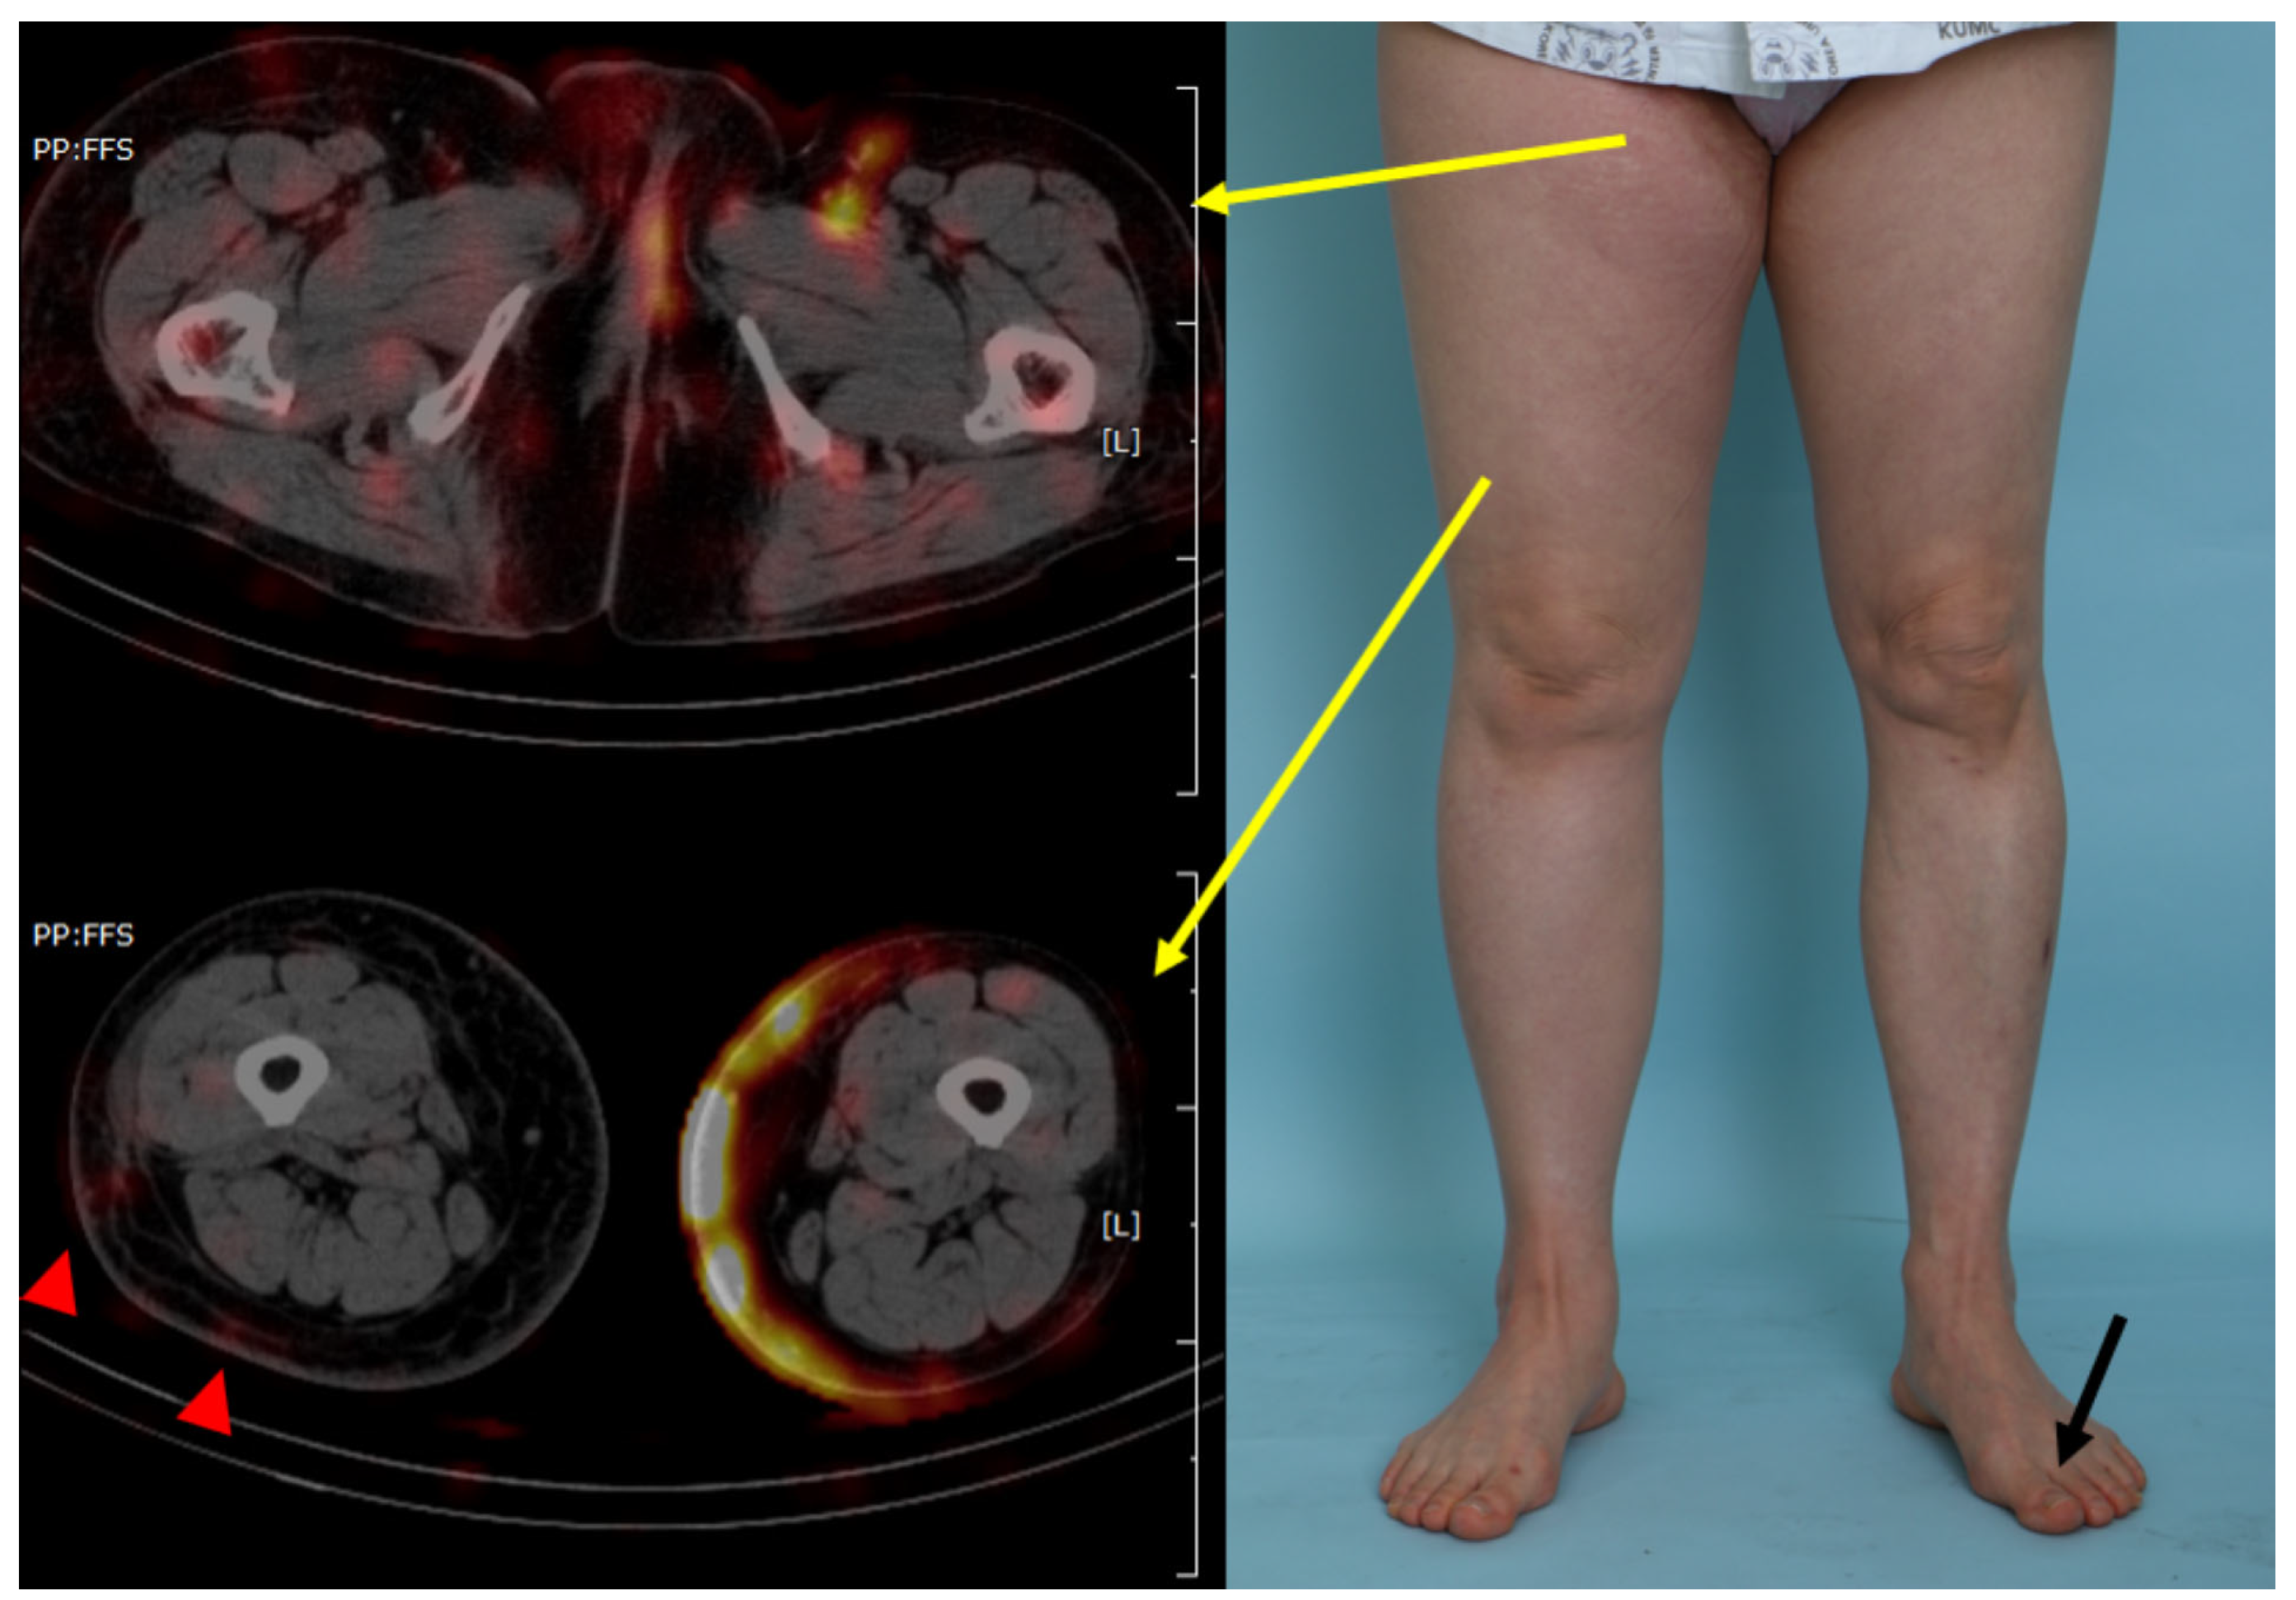

| Negative finding (Neither pelvic retention nor retrograde lymphatic flow) | 3 (30.0%) |

| Pelvic retention only | 1 (10.0%) |

| Lower limb retrograde lymphatic flow only | 0 |

| Pelvic retention with lower limb retrograde lymphatic flow | 6 (60.0%) |

| Extent of lower limb retrograde lymphatic flow | |

| Thigh | 6 out of 6 (100%) |